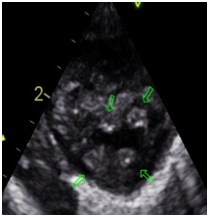

Usually they associated with aortic aneurysm, bicuspid aortic valve, aortic coarctation, subaortic stenosis, patent ductus arteriosus, abnormal interatrial and interventricular septum. They may evolve failure and / or mitral stenosis. (Figures 1–4)

Figure 3 Long Axis 5 cameras.